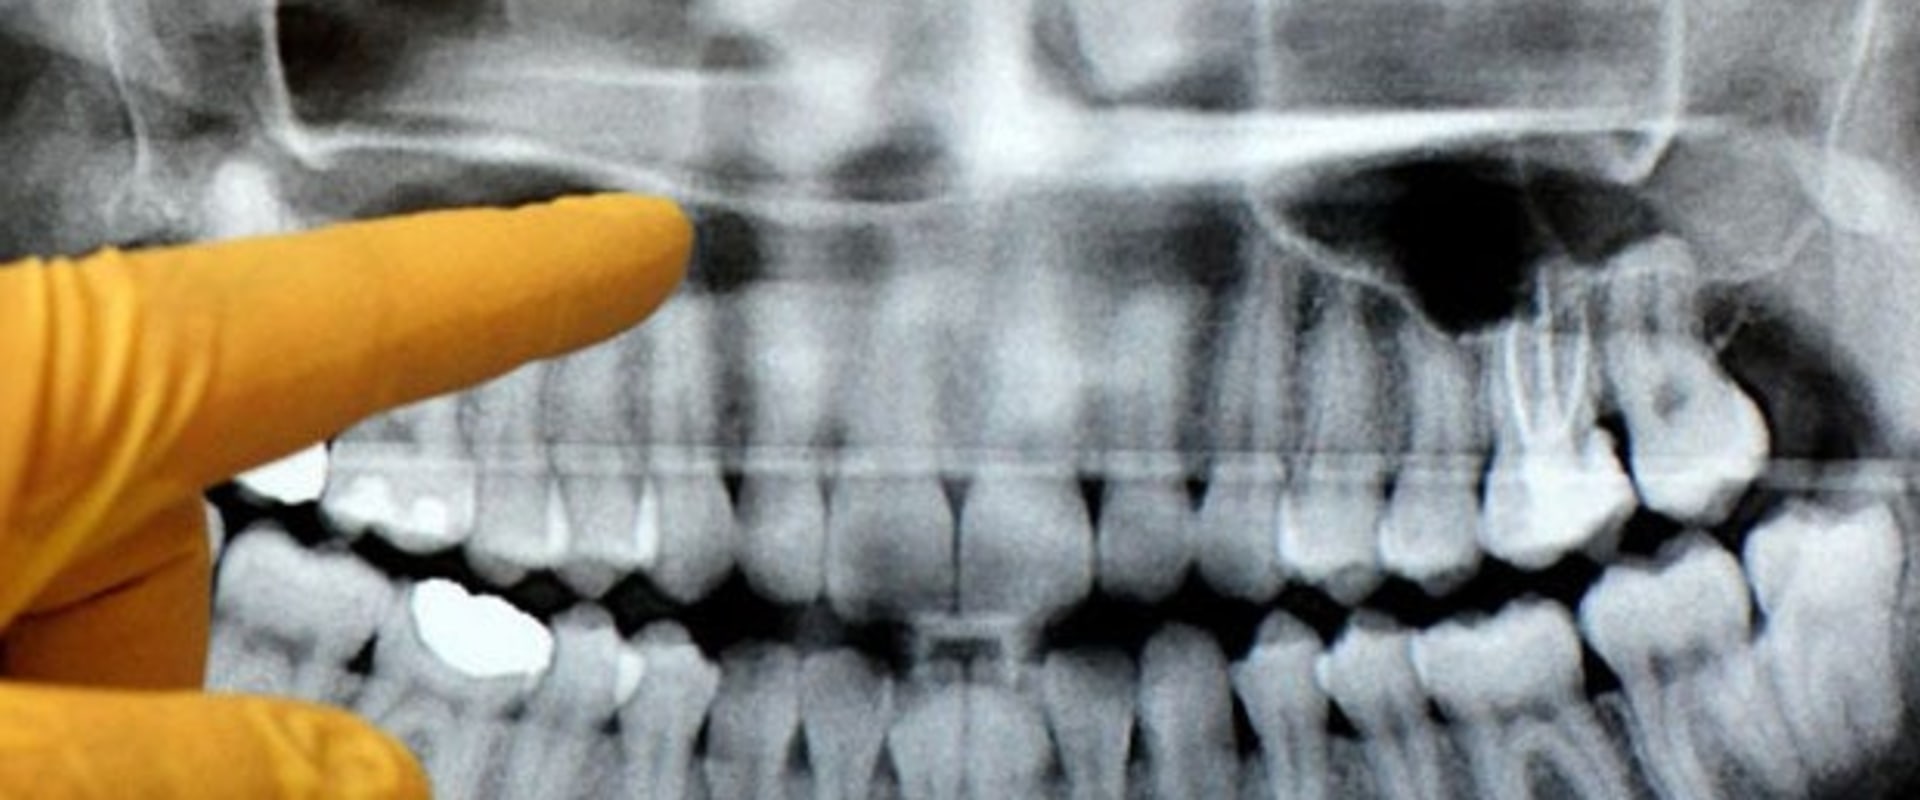

Common Errors That Can Occur In Panoramic Dental Radiography Include . errors and artefacts in dentomaxillofacial include positioning errors in intraoral techniques, panoramic. the focal plane (image layer) in panoramic radiography has limited dimensions; To know how to recognize and correct errors seen in panoramic radiographs. the most common positioning errors that resulted in a retake or repeated panoramic radiographic examination were. it is important for the clinician to be able to understand errors when they occur and how to correct them. this study was performed to determine the relative frequency of positioning errors, to identify those errors. dental radiography is the process of making pictures of teeth and the tissues around them by exposing image receptors to x.